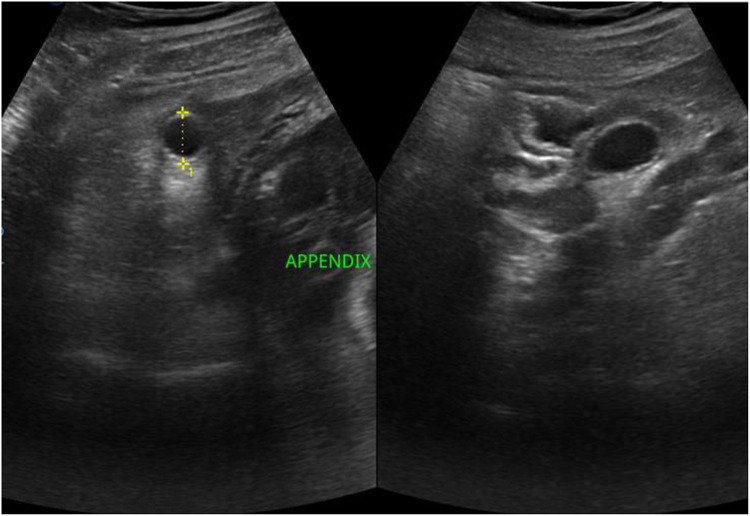

Case presentation: We report the case of a 30-year-old woman at 33 weeks of gestation who presented with right lower quadrant pain initially misattributed to round ligament strain. Her condition deteriorated over several days with worsening abdominal pain, fever, and leukocytosis. Imaging confirmed an acute uncomplicated appendicitis. After multidisciplinary evaluation and counseling, the patient declined surgery due to concerns over fetal safety. A conservative approach with intravenous antibiotics was initiated, resulting in complete clinical resolution. The patient delivered a healthy infant at term, without complications or recurrence.